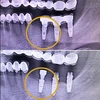

Diş Eksikliği